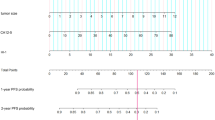

Figure 1 shows the distribution of SUV indices and the MTV of the 35 tumor samples.

There was no significant difference in the MTV among TNM classification, tumor location, and patient’s age. Tumors (n = 35) were divided into low-MTV and high-MTV tumors based on the median value of MTV (9.26 cm3).